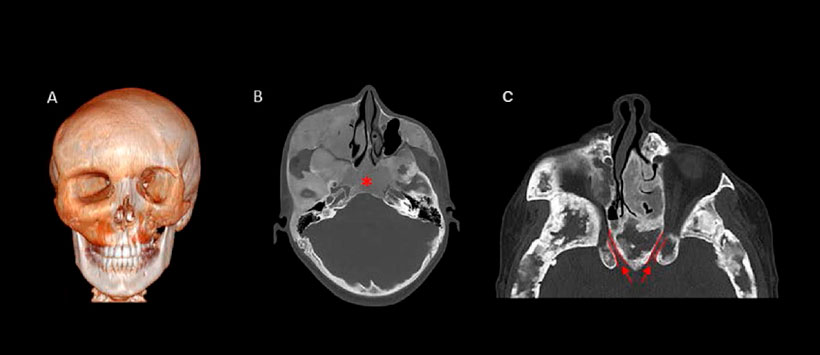

Figura 3: Displasia fibrosa poliostótica craneofacial. (A) TC 3D de un varón de 17 años, que muestra una enfermedad extensa de la asimetría orbital y de la parte media de la cara. (B) TC muestra la apariencia típica de “vidrio esmerilado” de la cara media izquierda y la base del cráneo, borrando la región de los senos esfenoidales (asterisco). (C) TC de una mujer de 33 años que muestra el estrechamiento de los canales ópticos bilaterales (delineado en rojo).